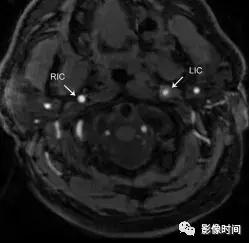

7.短暂颈动脉周围炎症:也称为 Fay 综合征,患者多表现为单侧颈总动脉分叉区域持续性搏动疼痛,具有自限性,往往 1-2 周缓解,首选激素治疗。虽然目前发病机制存在争议,但是大多数认为与颈总动脉分叉区域的特发性炎症有关,因此,又被称为短暂颈动脉周围炎症。CT、MRI 显示颈动脉周围软组织异常、劲动脉壁增厚,特别是分叉处,管腔一般不受影响,CT 一般为低密度,T1WI 压脂序列呈稍低信号(区别于夹层高信号),增强扫描呈明显强化,激素治疗随访后消失。

CTA 显示轴向左侧颈总动脉分叉区周围软组织增厚(无尾箭头),管腔未见狭窄,可见软斑块(长箭头)。TOFMRA 显示左颈内动脉周围软组织增厚,注意右颈内动脉的正常外观。冠状 T1WI+C 显示左侧颈内动脉周围明显强化 (长箭头),注意右颈内动脉的正常外观。激素治疗随访约 4 个月后,冠状 T1WI+C 显示颈内动脉周围厚度减轻。